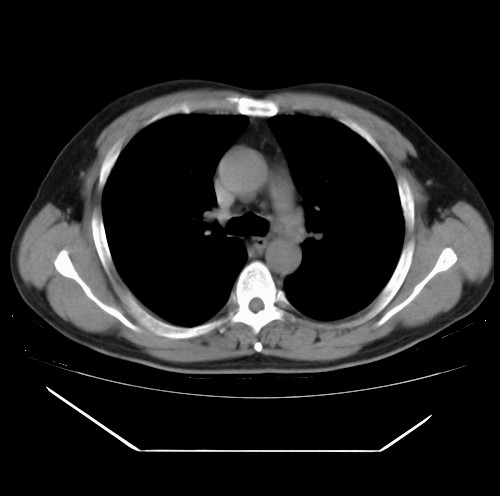

标题: CT22085:双肺多发结节

男,44岁,咳嗽,痰中带血2天。

除肺内及胸膜下可见多发大结节外,在肺小叶中心核、小叶间隔及支气管血管束上亦可见多方小结节,可以认为是随机分布。考虑转移可能性大。

仔细观察病灶形态,病灶边界部分清楚,结合临床症状,首先考虑转移,纵隔内多个肿大淋巴结影。

双肺血管纹理末端多发类圆形结节,边界光滑清晰 气管前腔静脉后淋巴结肿大

考虑转移瘤

沿血管分布,位于血管末端。转移瘤多见,血行性菌栓也可见到。

本例双肺多发类圆形高密度灶,边清,结合病史多考虑双肺多发转移改变,可以结合实验室检查。